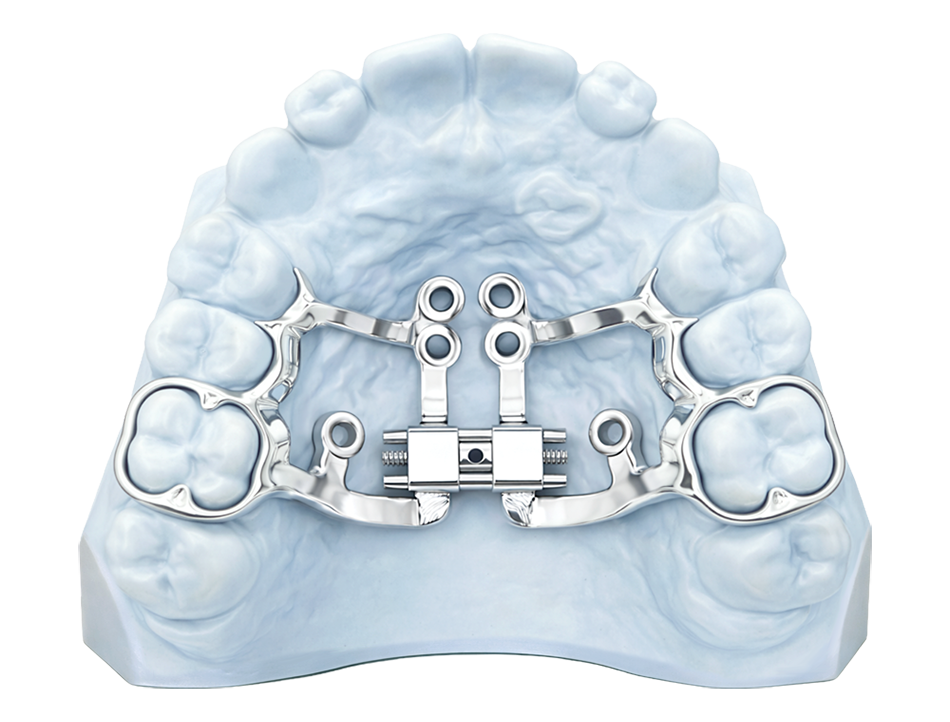

FULLY CUSTOM MARPE

A Fully Custom MARPE is digitally planned from start to finish and manufactured to the patient’s anatomy using advanced imaging and intraoral scan data. This level of customization supports precise appliance design, improved fit, and a high degree of predictability, offering a refined solution for clinicians seeking maximum control and accuracy.

Best For:

- Complex Or High-Precision Expansion Cases.

- Practices Utilizing Cbct-Guided Planning.

- Clinicians Seeking Maximum Control And Predictability.

Fully Custom Options:

- Fully Custom Framework

- 3D Metal Printed Bands

- Multiple Mid-Line Screw Options

Surgical Guide Available